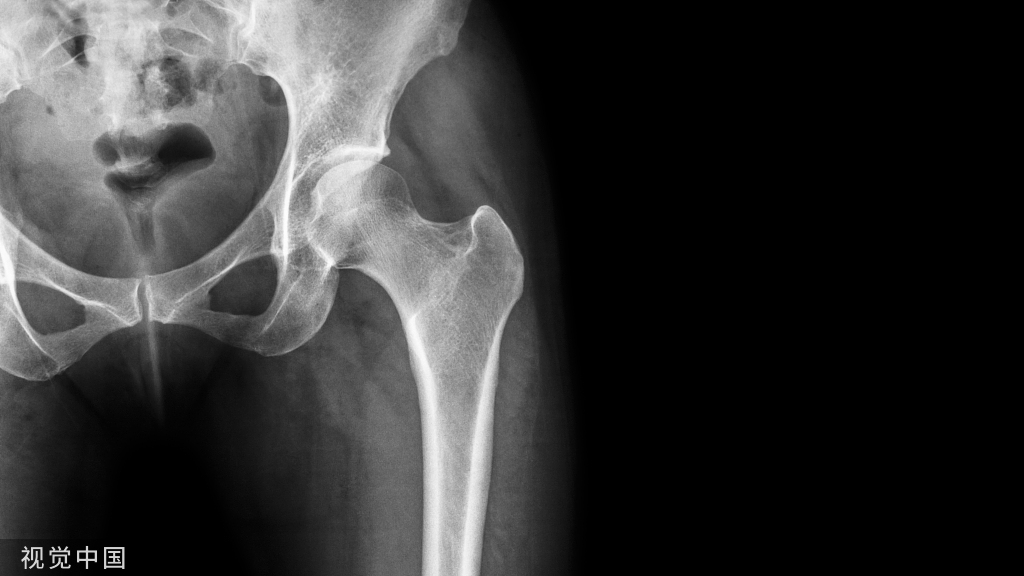

并建议保守治疗无效的青年战士A、B型腰椎峡部裂病例采用椎弓根螺钉固定,峡部自体髂骨原位植骨融合率高,效果好,C型战士峡部裂则宜采用后路椎间植骨融合椎弓根螺钉内固定术。